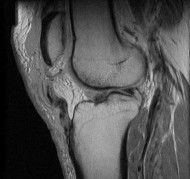

Question 13:

During posterior cruciate ligament (PCL) reconstruction, understanding bundle biomechanics is essential. Which of the following best describes the function and tensioning pattern of the native PCL bundles?

Options:

- The anterolateral bundle is the primary restraint to posterior translation in extension and is lax in flexion

- The posteromedial bundle is the primary restraint to posterior translation at 90 degrees of flexion

- The anterolateral bundle is the primary restraint to posterior translation at 90 degrees of flexion and tightens in flexion

- The posteromedial bundle is the primary restraint to internal rotation at 30 degrees of flexion

- Both bundles are equally tensioned throughout the entire arc of motion

Correct Answer: The anterolateral bundle is the primary restraint to posterior translation at 90 degrees of flexion and tightens in flexion

Explanation:

The PCL consists of the larger anterolateral (AL) bundle and the smaller posteromedial (PM) bundle. The AL bundle is lax in extension and becomes tight in flexion, acting as the primary restraint to posterior tibial translation at 90 degrees of knee flexion. Conversely, the PM bundle is tight in extension and lax in flexion.